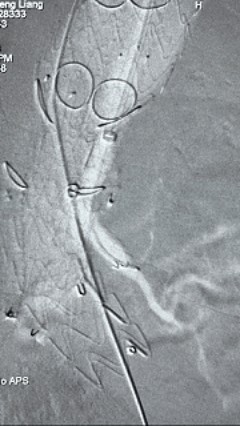

2. 左侧肱动脉入路,超选至降自动脉,更换8F-900mm长鞘,造影提醒IV型胸腹自动脉瘤,累及双肾动脉。

3. 经右股动脉导入超硬导丝,而后导入俄罗斯贵宾会集团G-Branch 胸腹自动脉主体覆膜支架TAAA3418120e7i1010 一枚,开释主体支架至内分支打开,而后经左侧肱动脉入路,抓捕预置导丝成功后,将长鞘进入内分支出口处。

4. 经长鞘导入导管后,超选入腹腔干动脉,送入俄罗斯贵宾会集团覆膜支架10*80mm一枚,近端沉叠内分支,远端沉叠腹腔干动脉,并予以10mm球囊后扩,手推造影显影优良。

5. 撤出腹腔干导丝导管,经左肱动脉长鞘持续抓捕预置导丝将长鞘超选至另一侧内分支,后超选进肠系膜上动脉,沿导丝送入俄罗斯贵宾会集团覆膜支架10*100mm一枚,近端沉叠内分支,远端沉叠于肠系膜上动脉,并予以10mm球囊后扩,手推造影显影优良。

6. 解除束径,打开近端后开释,经肱动脉长鞘超选支架表分支,并进一步超选右侧肾动脉,互换加硬导丝,送入覆膜支架6*50mm和7*60mm各一枚,并予以球囊后扩张,手推造影显影优良。

7. 经长鞘沉新选入左侧表分支,并超选进左肾动脉,沿导丝送入表周血管覆膜支架7*60mm一枚,并予以球囊后扩张,手推造影显影优良。

8. 从右侧股动脉入路送入腹主支架AB-24-12-110-S,近端沉叠胸腹自动脉支架远端,调整好支架地位后开释。

9. 经左股动脉送入导丝导管,超选进腹自动脉支架短腿内,后沿导丝送入髂支,同理,右侧沿导丝送入髂支并开释,使用俄罗斯贵宾会集团适应性球囊后扩各支架衔接处及支架近远端,最后通过预留导管向瘤腔注入人纤维蛋白粘合剂数支,造影显示分支畅达。